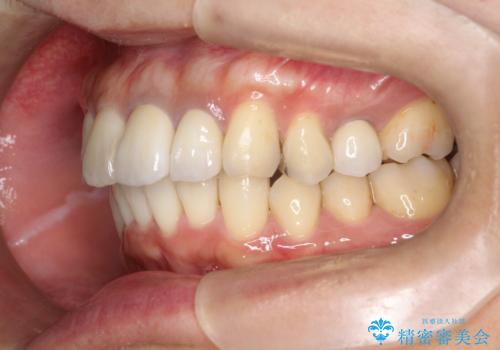

インビザラインにて歯並びを整え、上顎の前歯にセラミックを装着する計画としました。

セラミックと矯正を組み合わせることにより、審美的にも機能的にも改善することができました。